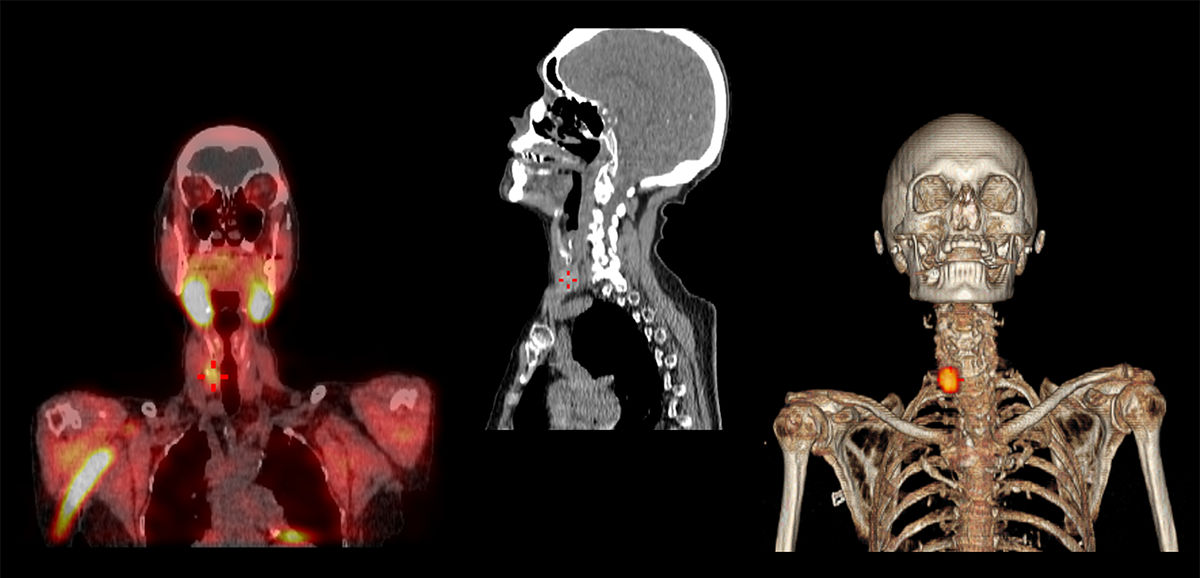

Contemporary nuclear medicine is a rapidly evolving healthcare discipline. It is a highly specialized division of radiology that utilizes functional imaging to characterize and track cellular changes of abnormal lesions. Understanding these structures at the molecular level enables more informed diagnoses and effective tracking of disease progression over time.

Designing a workplace infrastructure to support the complex operational requirements and technology needs for an efficient nuclear medicine department is key, says Declerck. As his facility expanded its investment in molecular imaging with a new positron emission tomography/computed tomography (PET/CT) scanner and digital single-photon emission computerized tomography/computed tomography (SPECT/CT) scanner, Declerck took the opportunity to optimize the layout of the department.